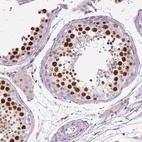

Immunohistochemical staining of human testis shows strong nuclear positivity in cells in seminiferous ducts.